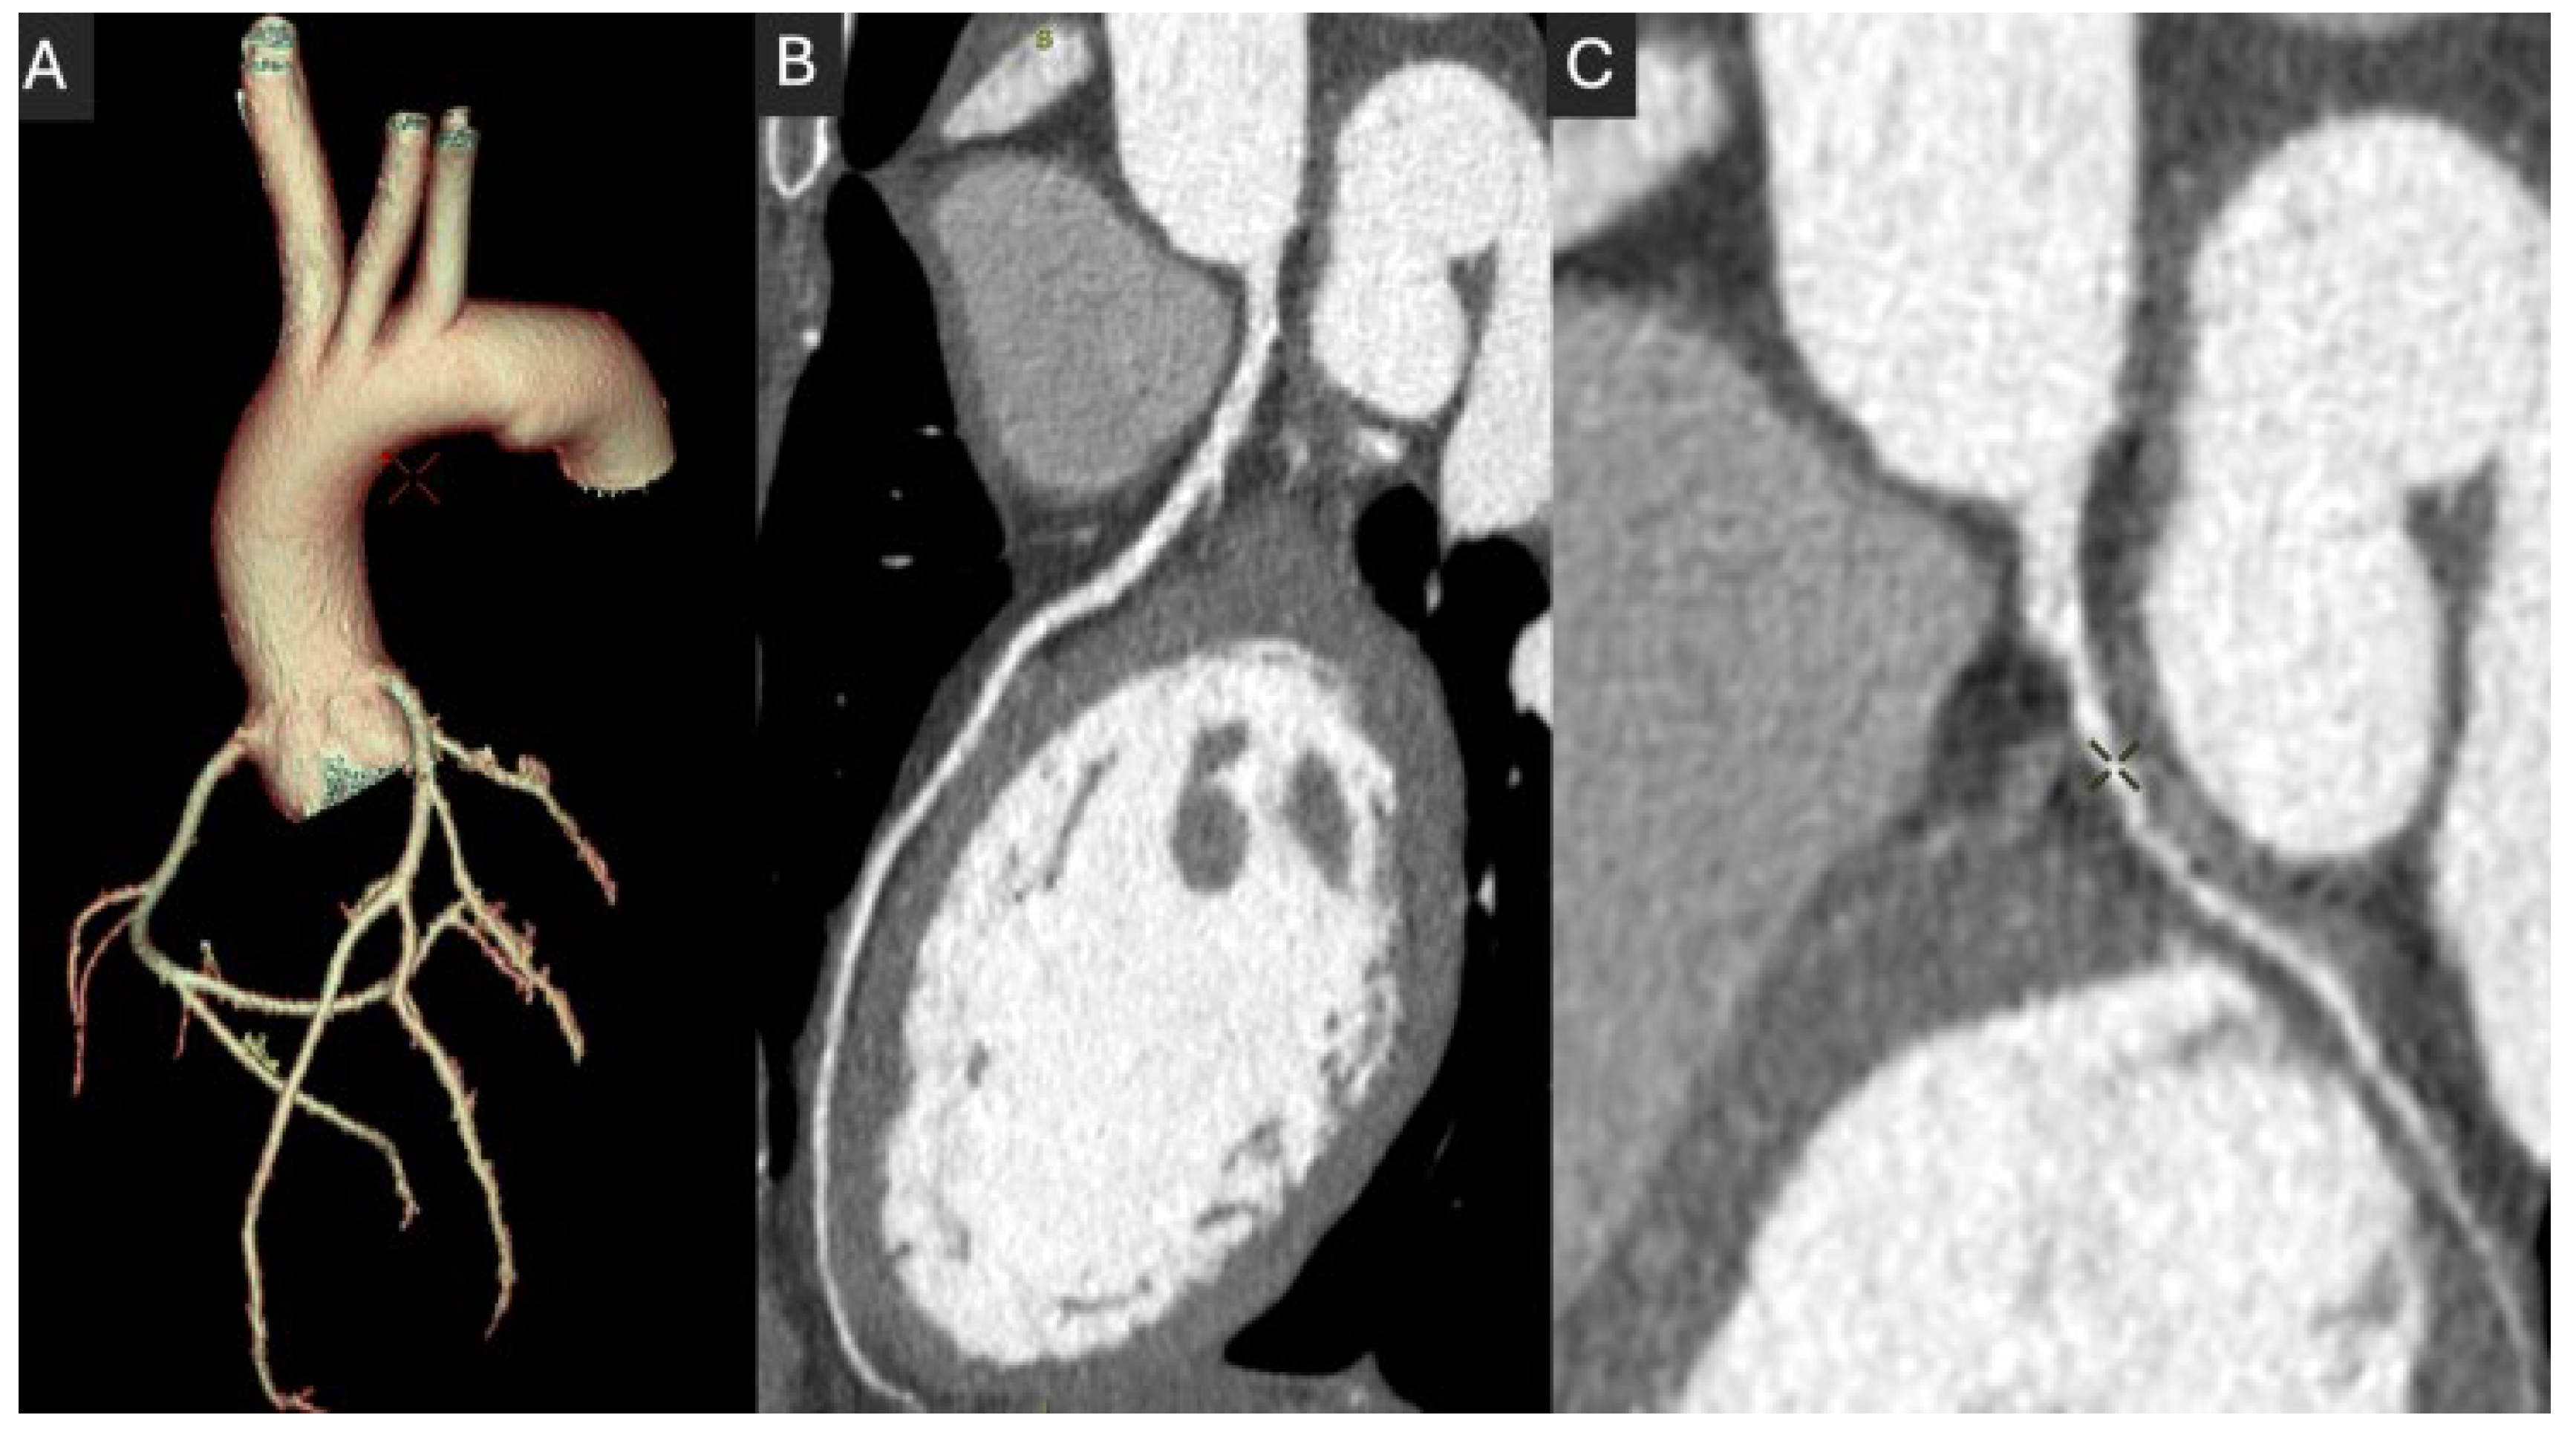

5.4. Spectral CT and Photon Counting CT

- Si-Mohamed, S.A.; Boccalini, S.; Lacombe, H.; Diaw, A.; Varasteh, M.; Rodesch, P.-A.; Dessouky, R.; Villien, M.; Tatard-Leitman, V.; Bochaton, T. Coronary CT Angiography with Photon-counting CT: First-In-Human Results. Radiology 2022, 303, 303–313. [Google Scholar] [CrossRef]

- Fahrni, G.; Boccalini, S.; Mahmoudi, A.; Lacombe, H.; Houmeau, A.; Elbaz, M.; Rotzinger, D.; Villien, M.; Bochaton, T.; Douek, P. Quantification of Coronary Artery Stenosis in Very-High-Risk Patients Using Ultra-High Resolution Spectral Photon-Counting CT. Investig. Radiol. 2025, 60, 114–122. [Google Scholar] [CrossRef]

- Rajiah, P.S.; Dunning, C.A.S.; Rajendran, K.; Tandon, Y.K.; Ahmed, Z.; Larson, N.B.; Collins, J.D.; Thorne, J.; Williamson, E.; Fletcher, J.G. High-Pitch Multienergy Coronary CT Angiography in Dual-Source Photon-Counting Detector CT Scanner at Low Iodinated Contrast Dose. Investig. Radiol. 2023, 58, 681–690. [Google Scholar] [CrossRef]

- Cundari, G.; Deilmann, P.; Mergen, V.; Ciric, K.; Eberhard, M.; Jungblut, L.; Alkadhi, H.; Higashigaito, K. Saving Contrast Media in Coronary CT Angiography with Photon-Counting Detector CT. Acad. Radiol. 2024, 31, 212–220. [Google Scholar] [CrossRef]